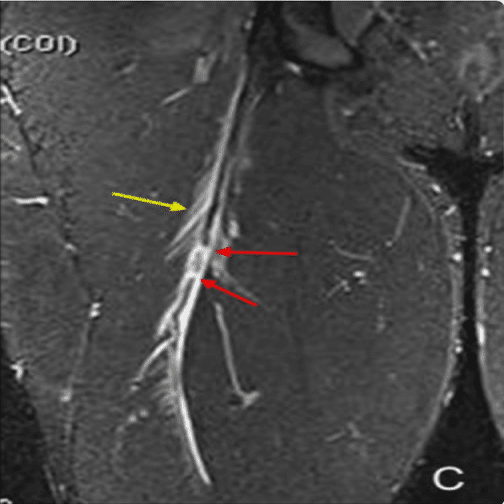

◉損傷後の修復が得られにくい大腿二頭筋遠位部損傷

(Distal Musculotendinous T Junction:DMTJ)

(Entwisle T, Ling Y, Splatt A, Brukner P, Connell D. Distal Musculotendinous T Junction Injuries of the Biceps Femoris: An MRI Case Review. Orthop J Sports Med. 2017 から引用)